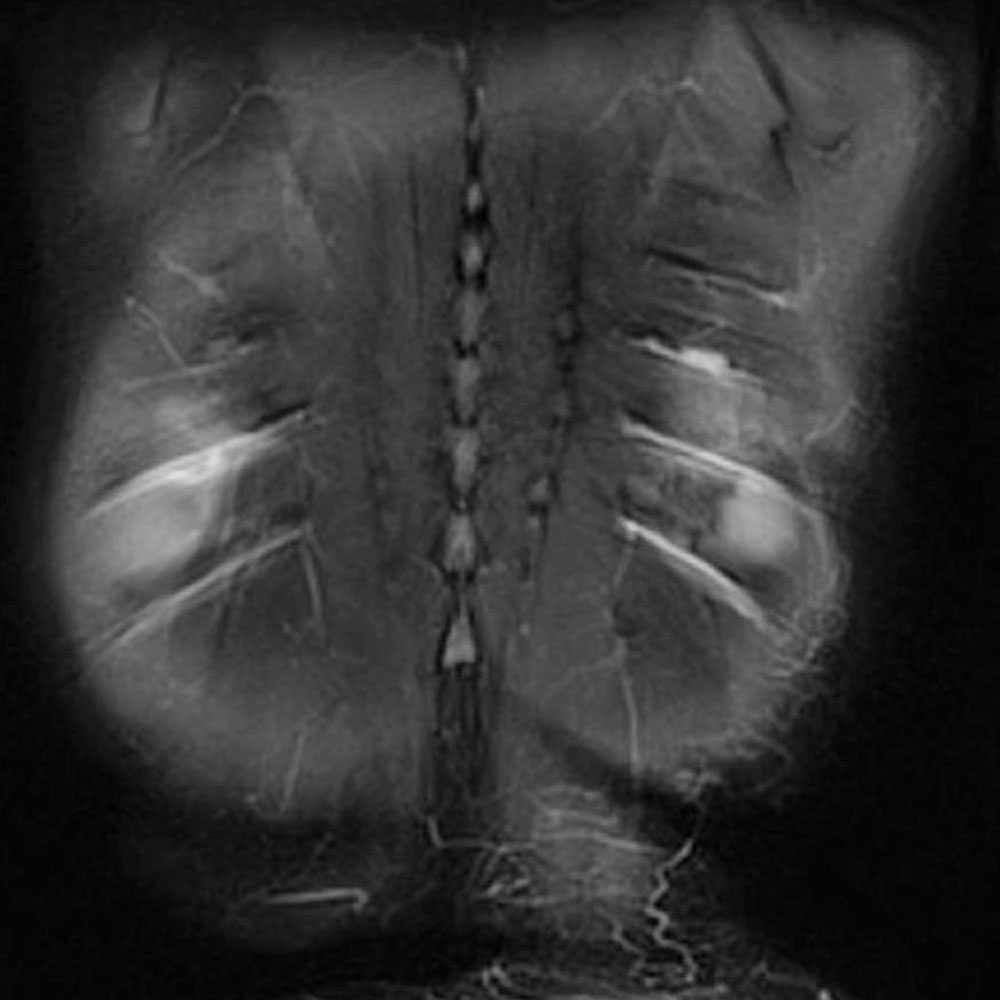

One lymphatic malformation in children that involves the abdomen is Central Conducting Lymphatic Anomaly (CCLA). This is defined as inadequate central drainage of the major trunk lymphatics due to dysmotility, stenosis, or aplasia of the main central abdominal and/or thoracic lymphatic ducts. Insufficient drainage due to congenital malformations of the thoracic duct or cisterna chyli results in lymphostasis with consecutive peripheral lymphatic hypertension and reflux in various organ systems, depending on the location of the drainage obstruction. In this context, thoracic lymphatic hypertension can lead to pulmonary lymphatic hypertension with recurrent chylous pleural effusions or lymphatic congestion of the lungs with plastic bronchitis. Abdominal outflow obstruction (e.g., dysplasia or aplasia of the cisterna chyli) can result in protein-losing enteropathy, chylous ascites, abdominal lymphatic cysts, and/or reflux and retention of lymphatic fluid into one or both extremities (lymphedema of the leg) or the genital region. The pent-up lymphatic pressure can in turn lead to leakage of lymphatic fluid through the skin (lymphorrhea) or cutaneous lymphatic vesicles. Intranodal lymphangiography with ethiodized poppy seed oil injection into a punctured lymph node in the inguinal region can be very helpful in diagnosing this serious condition.